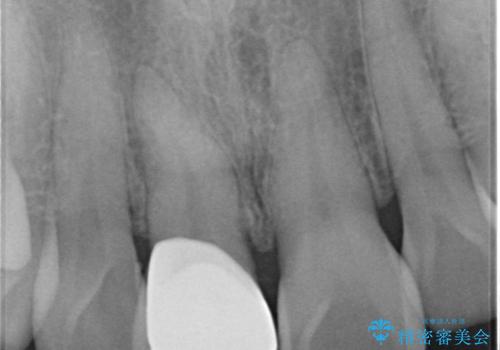

まず保険治療でコンポジットレジン修復を行い、神経の状態を確認した後、クラウンによる修復を行いました。

将来神経が失活する可能性もありますので経過観察する必要があります。